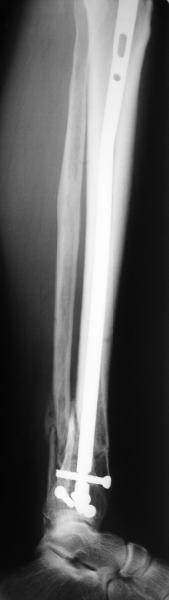

Very interesting application, but is the final position in a little distal varus with some fibula

distraction? Would that have been eliminated by fibula plating?

TDVC> little distal varus with some fibula distraction?

At least both the ankle mortise and tibial alignment look acceptable, don't they?